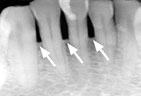

Advanced Periodontitis Advanced Periodontitis